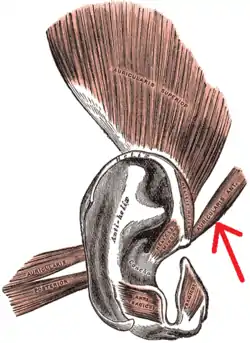

The muscles of the auricula. Anterior auricular is at right (indicated by the red arrow). | |